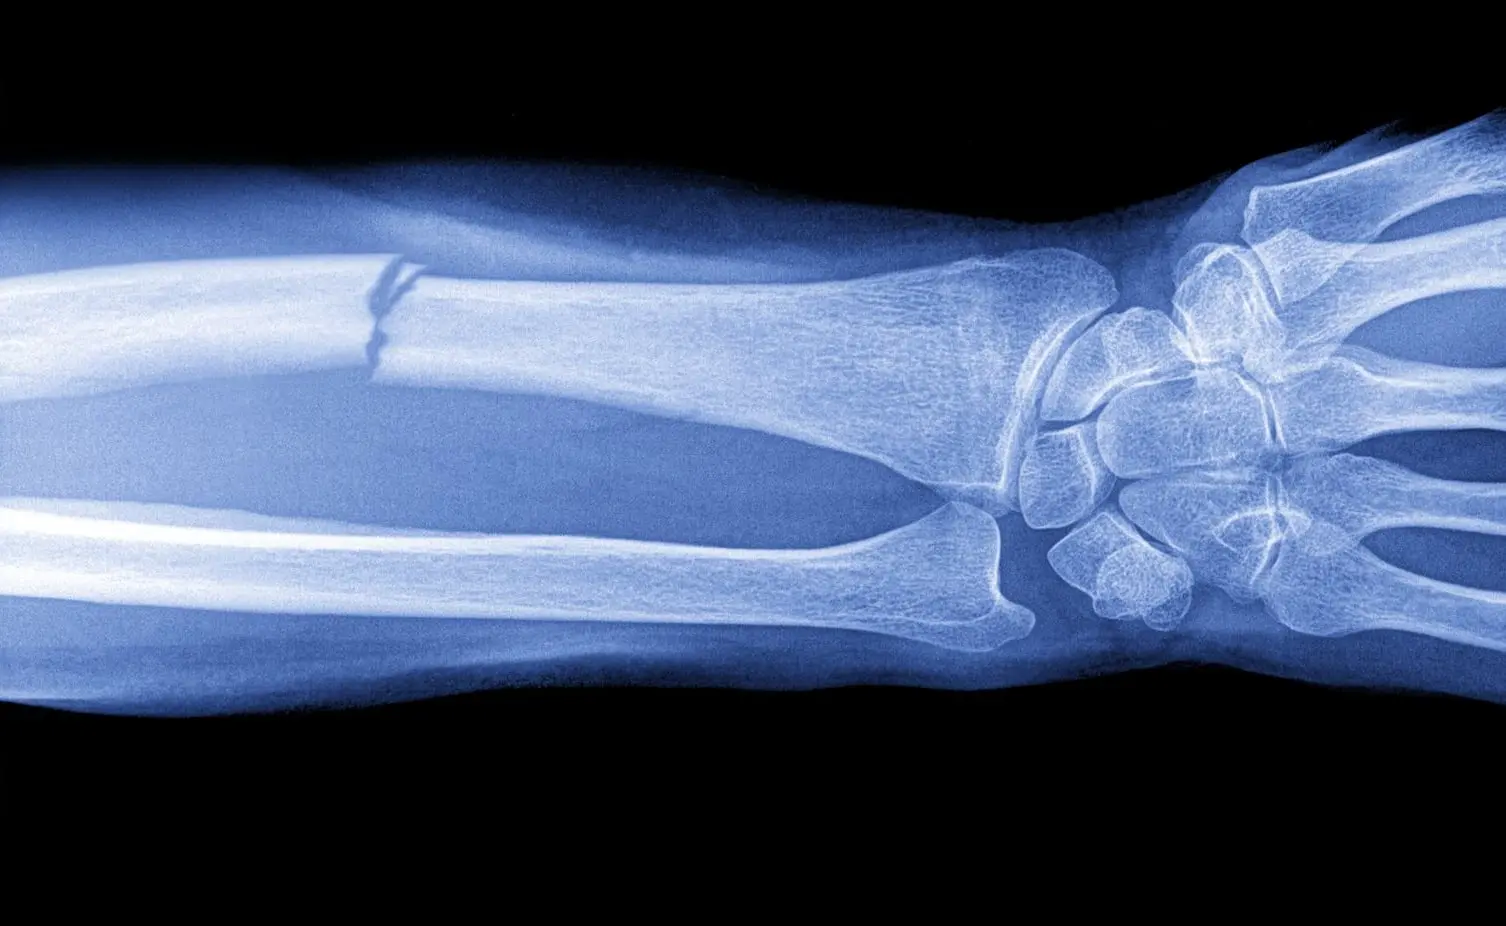

Восстановление костных дефектов – одна из важнейших задач современной медицины. Увеличение числа пациентов с травмами и заболеваниями опорно-двигательного аппарата требует поиска новых подходов к лечению, ведь традиционные методы не всегда позволяют добиться эффективного и стойкого результата. Старение населения, а также рост частоты серьезных повреждений приводят к активному развитию методов регенерации костей на клеточном уровне.

Естественные механизмы восстановления костей ограничены возможностями нашего организма: при незначительных травмах процессы регенерации идут успешно, однако при больших дефектах — свыше 2-3 сантиметров — самостоятельное заживление становится невозможным. Такая ситуация может привести к формированию ложных суставов, появлению рубцовой ткани и сохраняющимся дефектам, которые снижают качество жизни человека.